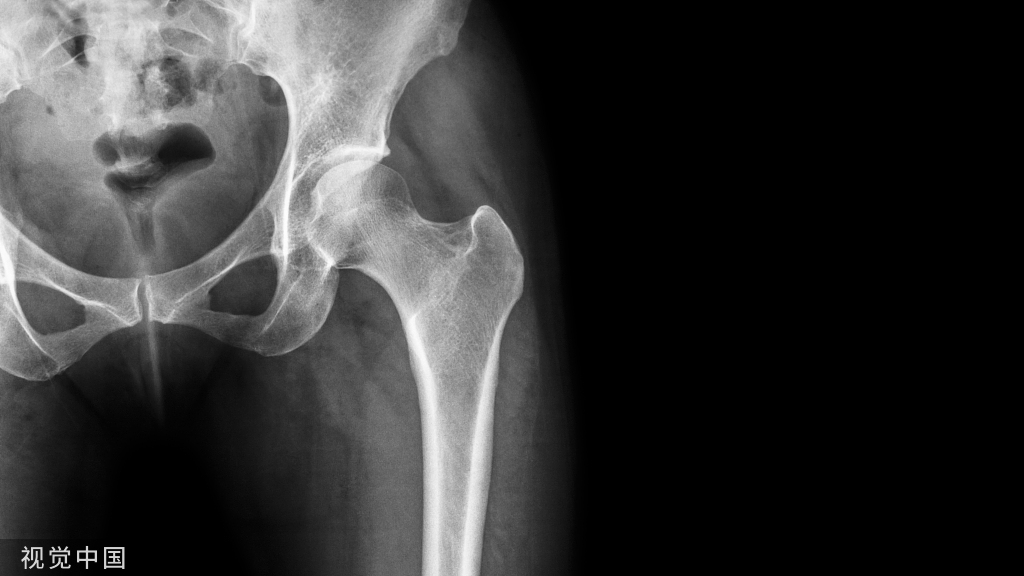

正确的拍摄方法: